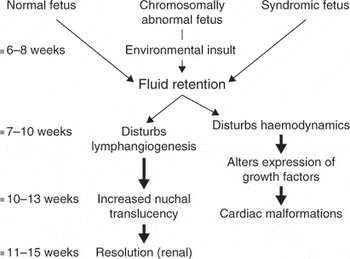

An exciting prospect to all this is that it seems likely that the ability to make the diagnosis of congenital cardiac disease so much closer to the timing of the insult which produces the cardiac malformation, might lead to the identification of the insult itself. My current understanding of the mechanism and chronology of increased nuchal translucency and congenital heart disease is seen in Figure 12. To summarise the current situation:

Figure 12. The cartoon shows the sequence of events which might produce increased nuchal translucency and cardiac malformations.